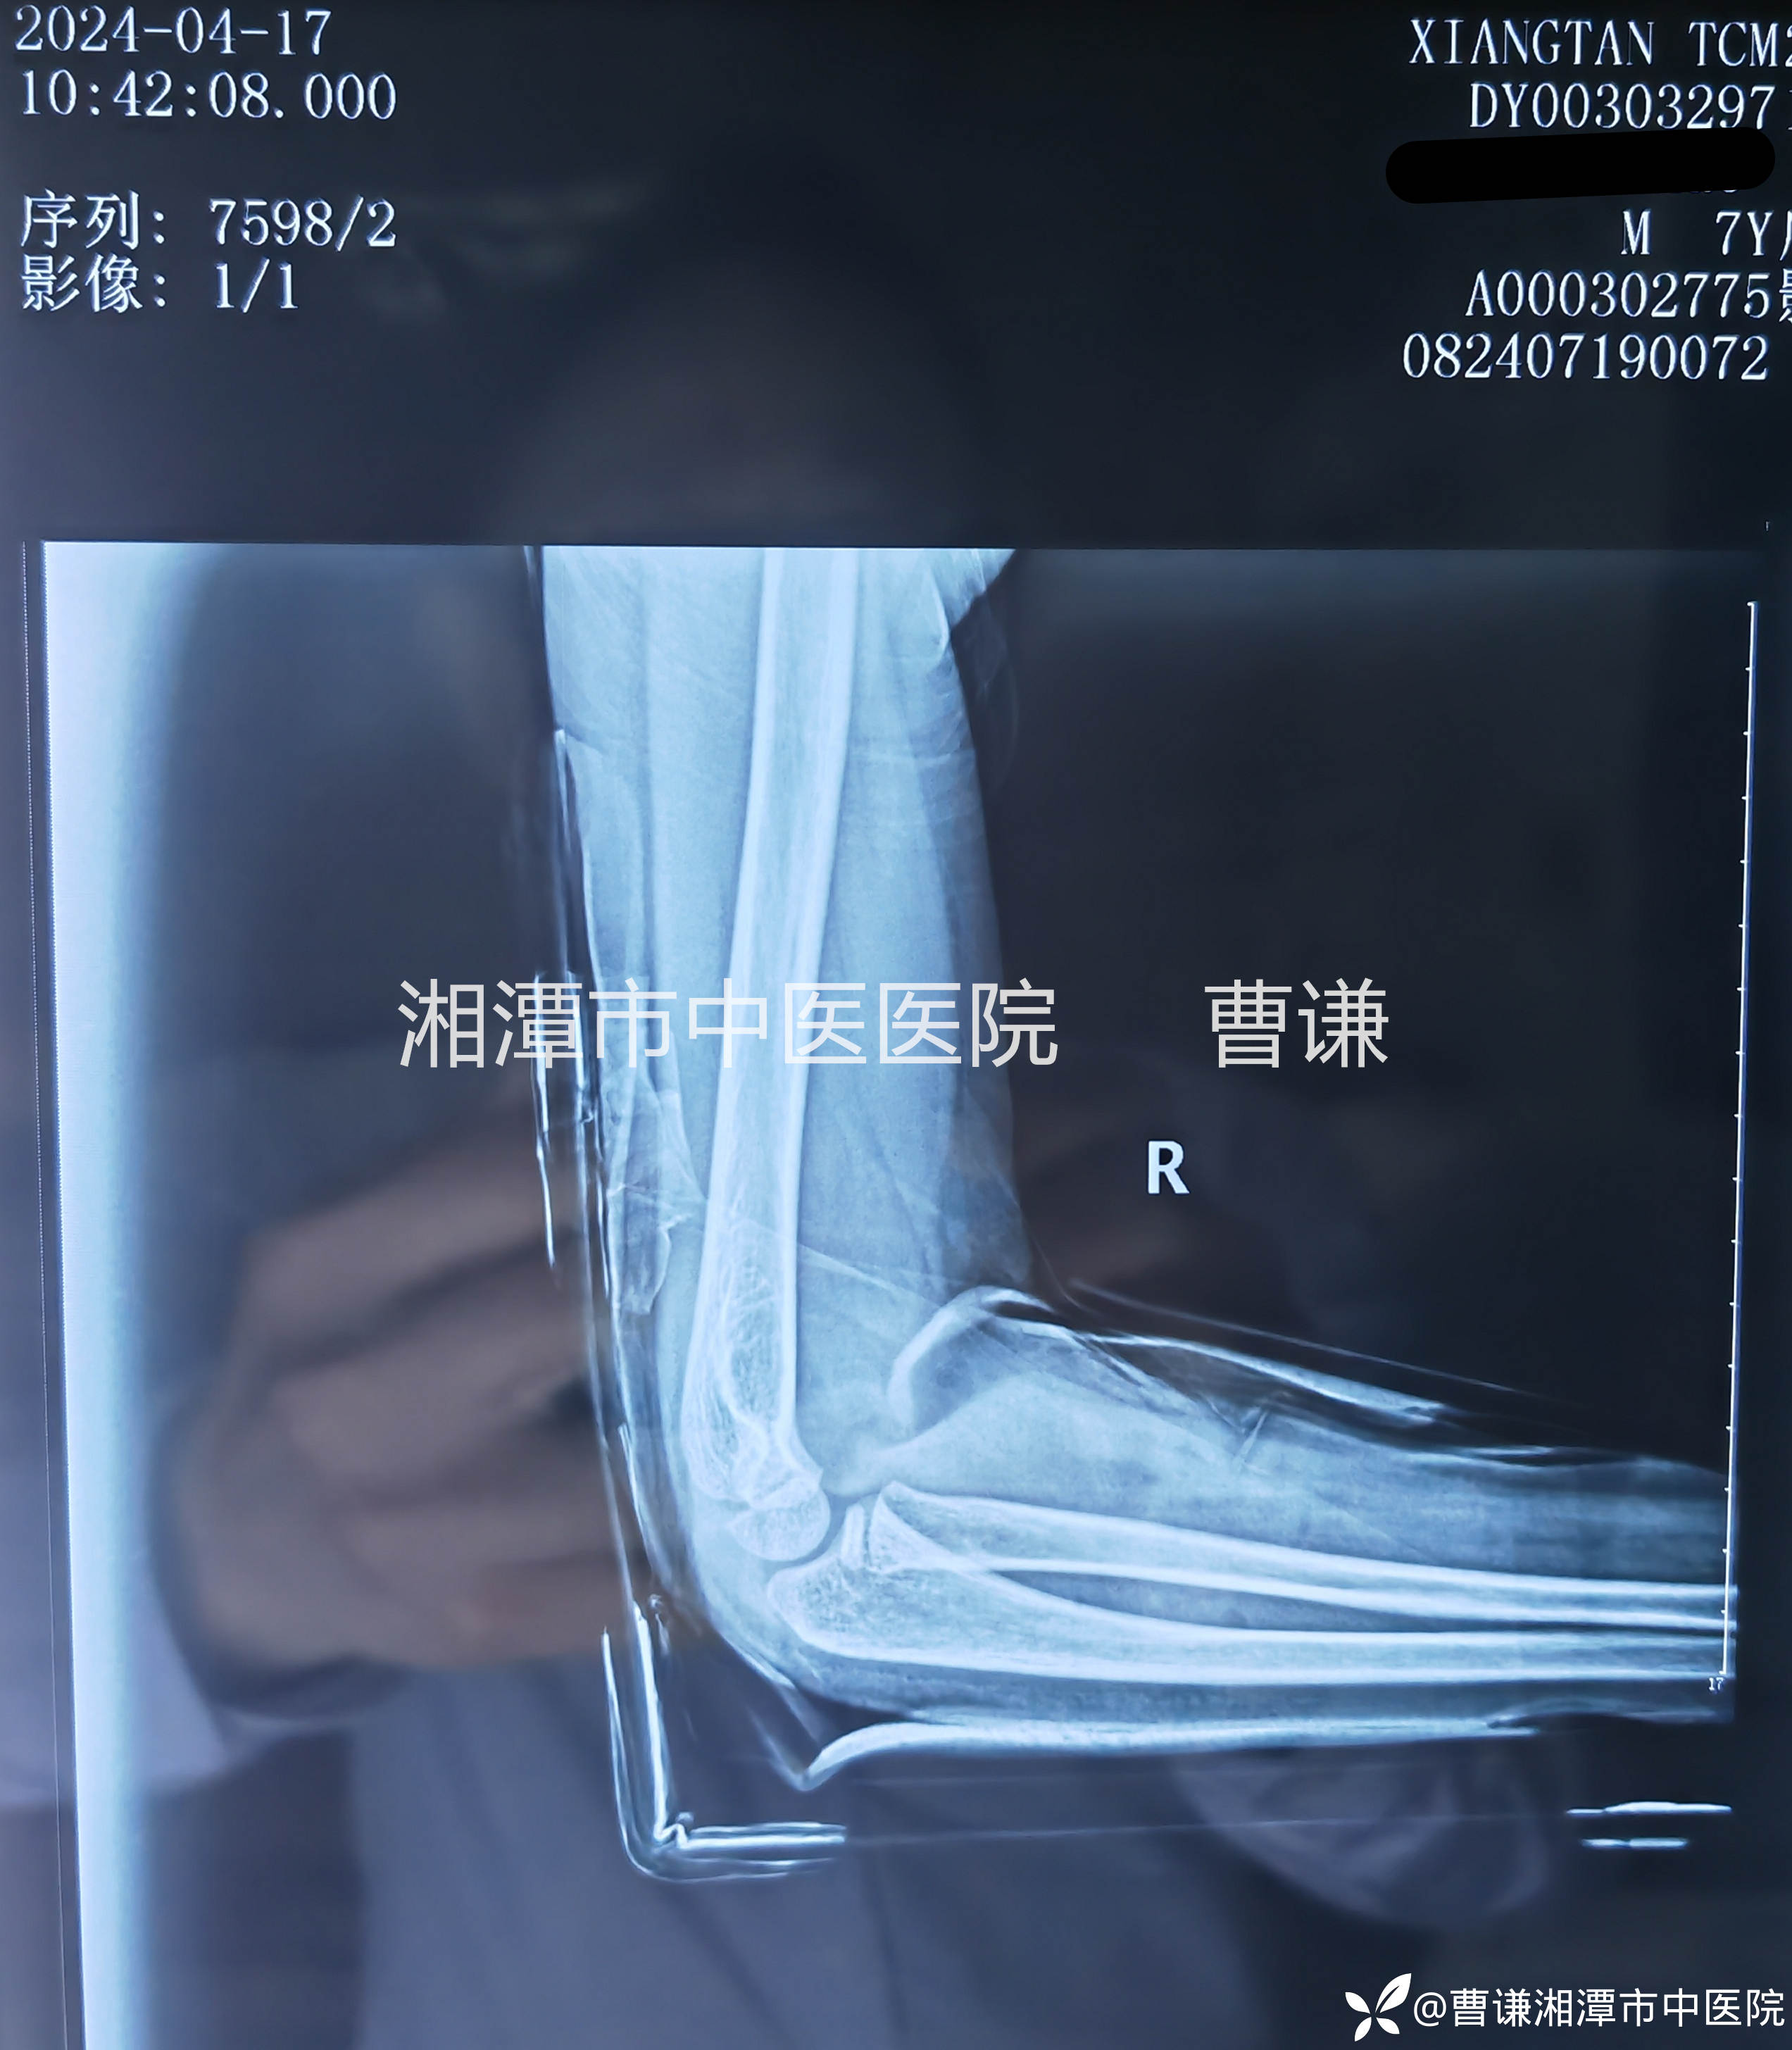

固定完成拍片复查示肱桡关节匹配良好。

伤后两周拍片复查未见明显异常,孩子就说一点都不痛了,小医生仔细体查局部无压痛,活动正常,主任指示拆除外固定,指导正常活动。